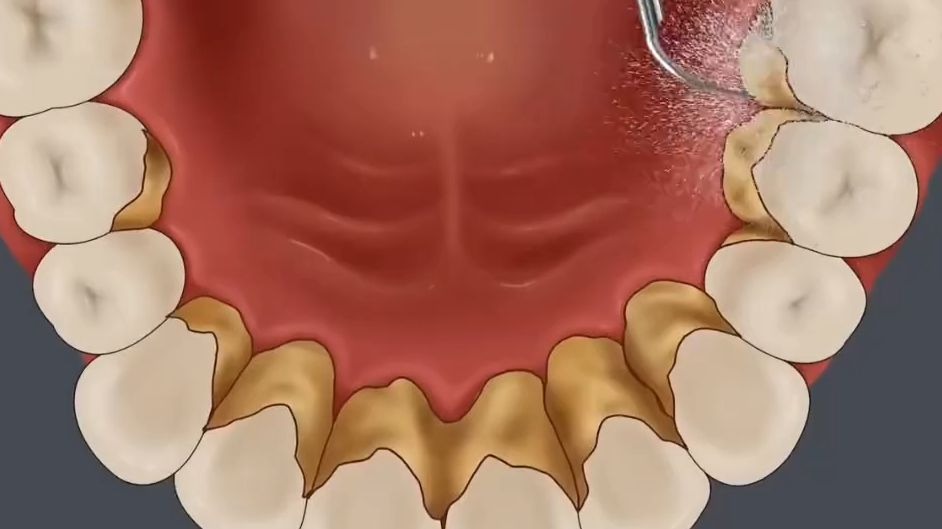

动画演示 清理牙结石过程

解压动画:我滴妈!这牙结石这么多!